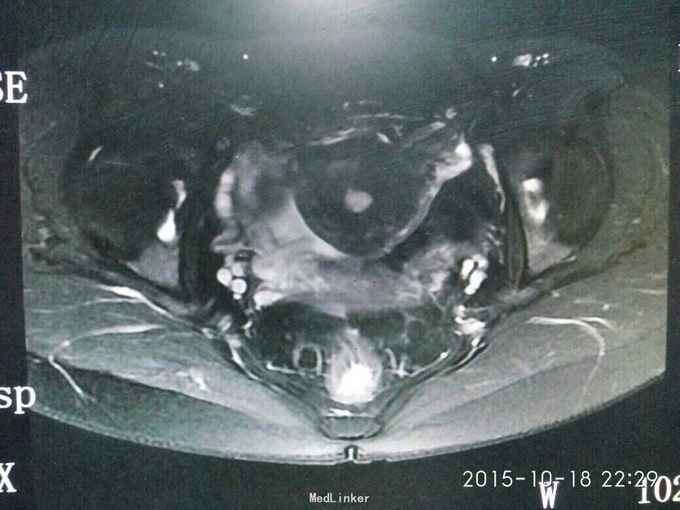

查体:妇检:外阴已婚已产式;阴道:畅,软,见少量淡黄色分泌物;宫颈少糜;子宫前位,鸭蛋大,无压痛;双侧附件未及异常。 辅助检查:我院病理会诊示:(子宫)低级别子宫内膜肉瘤。盆腔MRI示:子宫前壁近峡部肌层内异常信号。

诊断:子宫内膜间质肉瘤 治疗:全子宫+双侧附件切除术。术后病理报告示:(子宫)低级别子宫内膜间质肉瘤。宫旁、输卵管、卵巢未见癌组织累及。